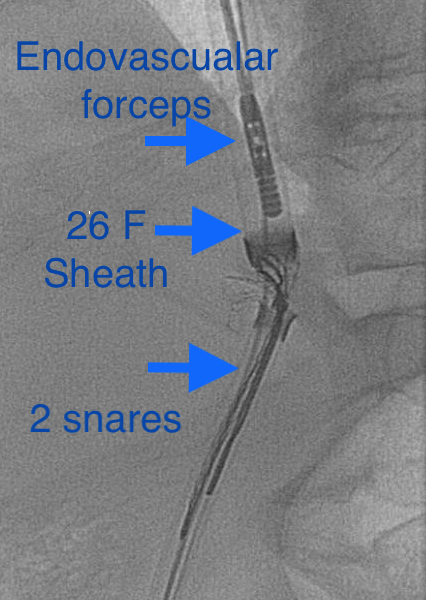

Pt presented to ED with CP, SOB. CXR shows embolized venous stent from OSH. Retrieved with 3 snares, 4 forceps, OR on standby,

@UABVascular help, 26F sheath, extra IR. Immediate symptom relief@SIRspecialists@SIRRFS@JVIRmedia#withoutascalpel#MIIPS#venous#embolize@uab_irpic.twitter.com/WpoUEt3P7z